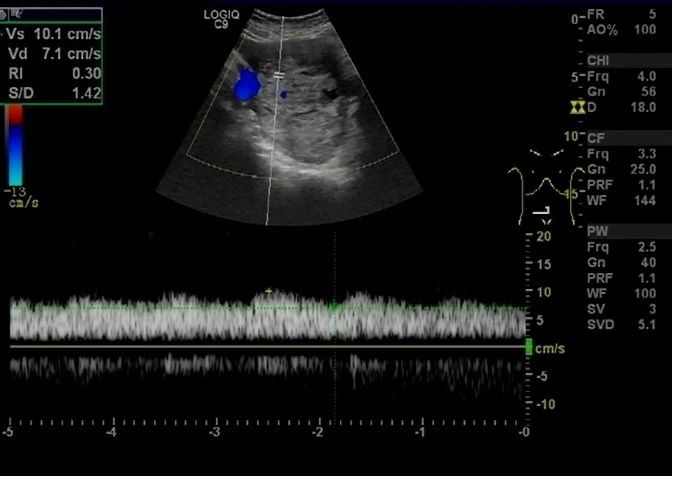

超声于右侧附件区见一囊实性团块,大小约 138 × 98 × 77 mm ,边界清,形态规则,内部回声不均,以实性为主(图 5), CDFI 于实性部分见少许血流信号(图 6), PW 测及低阻动脉血流频谱, RI:0.30 (图 7)。

图 7 PW 测及低阻动脉血流频谱, RI:0.30